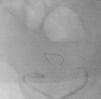

Neste contexto, decidiu-se efetuar angiografia invasiva por acesso arterial femoral direito. Este exame evidenciou fluxo muito escasso na artéria renal do enxerto e imagens hipotransparentes múltiplas e difusas, sugestivas de trombos organizados ao longo de todo o trajeto da artéria renal do rim transplantado (Figura 1). Procedeu-se a canulação seletiva com cateter de mamária interna e introdução na artéria renal de fio guia Balance Middleweight Universal II 0,14” (Abbott vascular®). De seguida, utilizando o sistema de aspiração por cateter Pronto V3 6F (vascular solutions, Inc.®), procedeu-se à aspiração de conteúdo intra-arterial, confirmando-se macroscopicamente a existência de material com aspecto trombótico (Figuras 2–4). Posteriormente, efetuou-se angioplastia com balão em toda a extensão da artéria renal (Figura 5). A melhoria angiográfica foi imediata, com visualização da sombra renal, evidenciando-se, no entanto, discretas irregularidades parietais (Figura 6). A terapêutica farmacológica adjuvante instituída consistiu em ácido acetilsalicílico (100mg/d), heparina não fracionada (5000U/bólus seguida de 100 U/kg/h) durante 72h e, subsequentemente, hipocoagulação oral com varfarina (INR alvo 2,0-3,0).